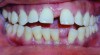

The American Association of Orthodontists recommends an orthodontic screening by age 7, or even earlier if a parent or a dentist discerns a problem.1 By this age, several permanent teeth in most children have erupted, allowing the orthodontist to effectively evaluate the orthodontic condition. The vast majority of 7-year-olds do not require orthodontic intervention. However, for the small percentage of those who do, if the problem is not discovered in a timely fashion, it may be difficult, if not impossible, to treat later in life. In addition, permanent and/or irreversible damage may already have been done (Figure 1). It is with this in mind that many orthodontic offices offer complimentary or minimally priced examinations and consultations to their patients, thus ensuring that no orthodontic problem is overlooked.

Figure 1 A 9-year-old patient with an untreated anterior crossbite exhibiting severe and irreversible gingival recession.

Figure 1